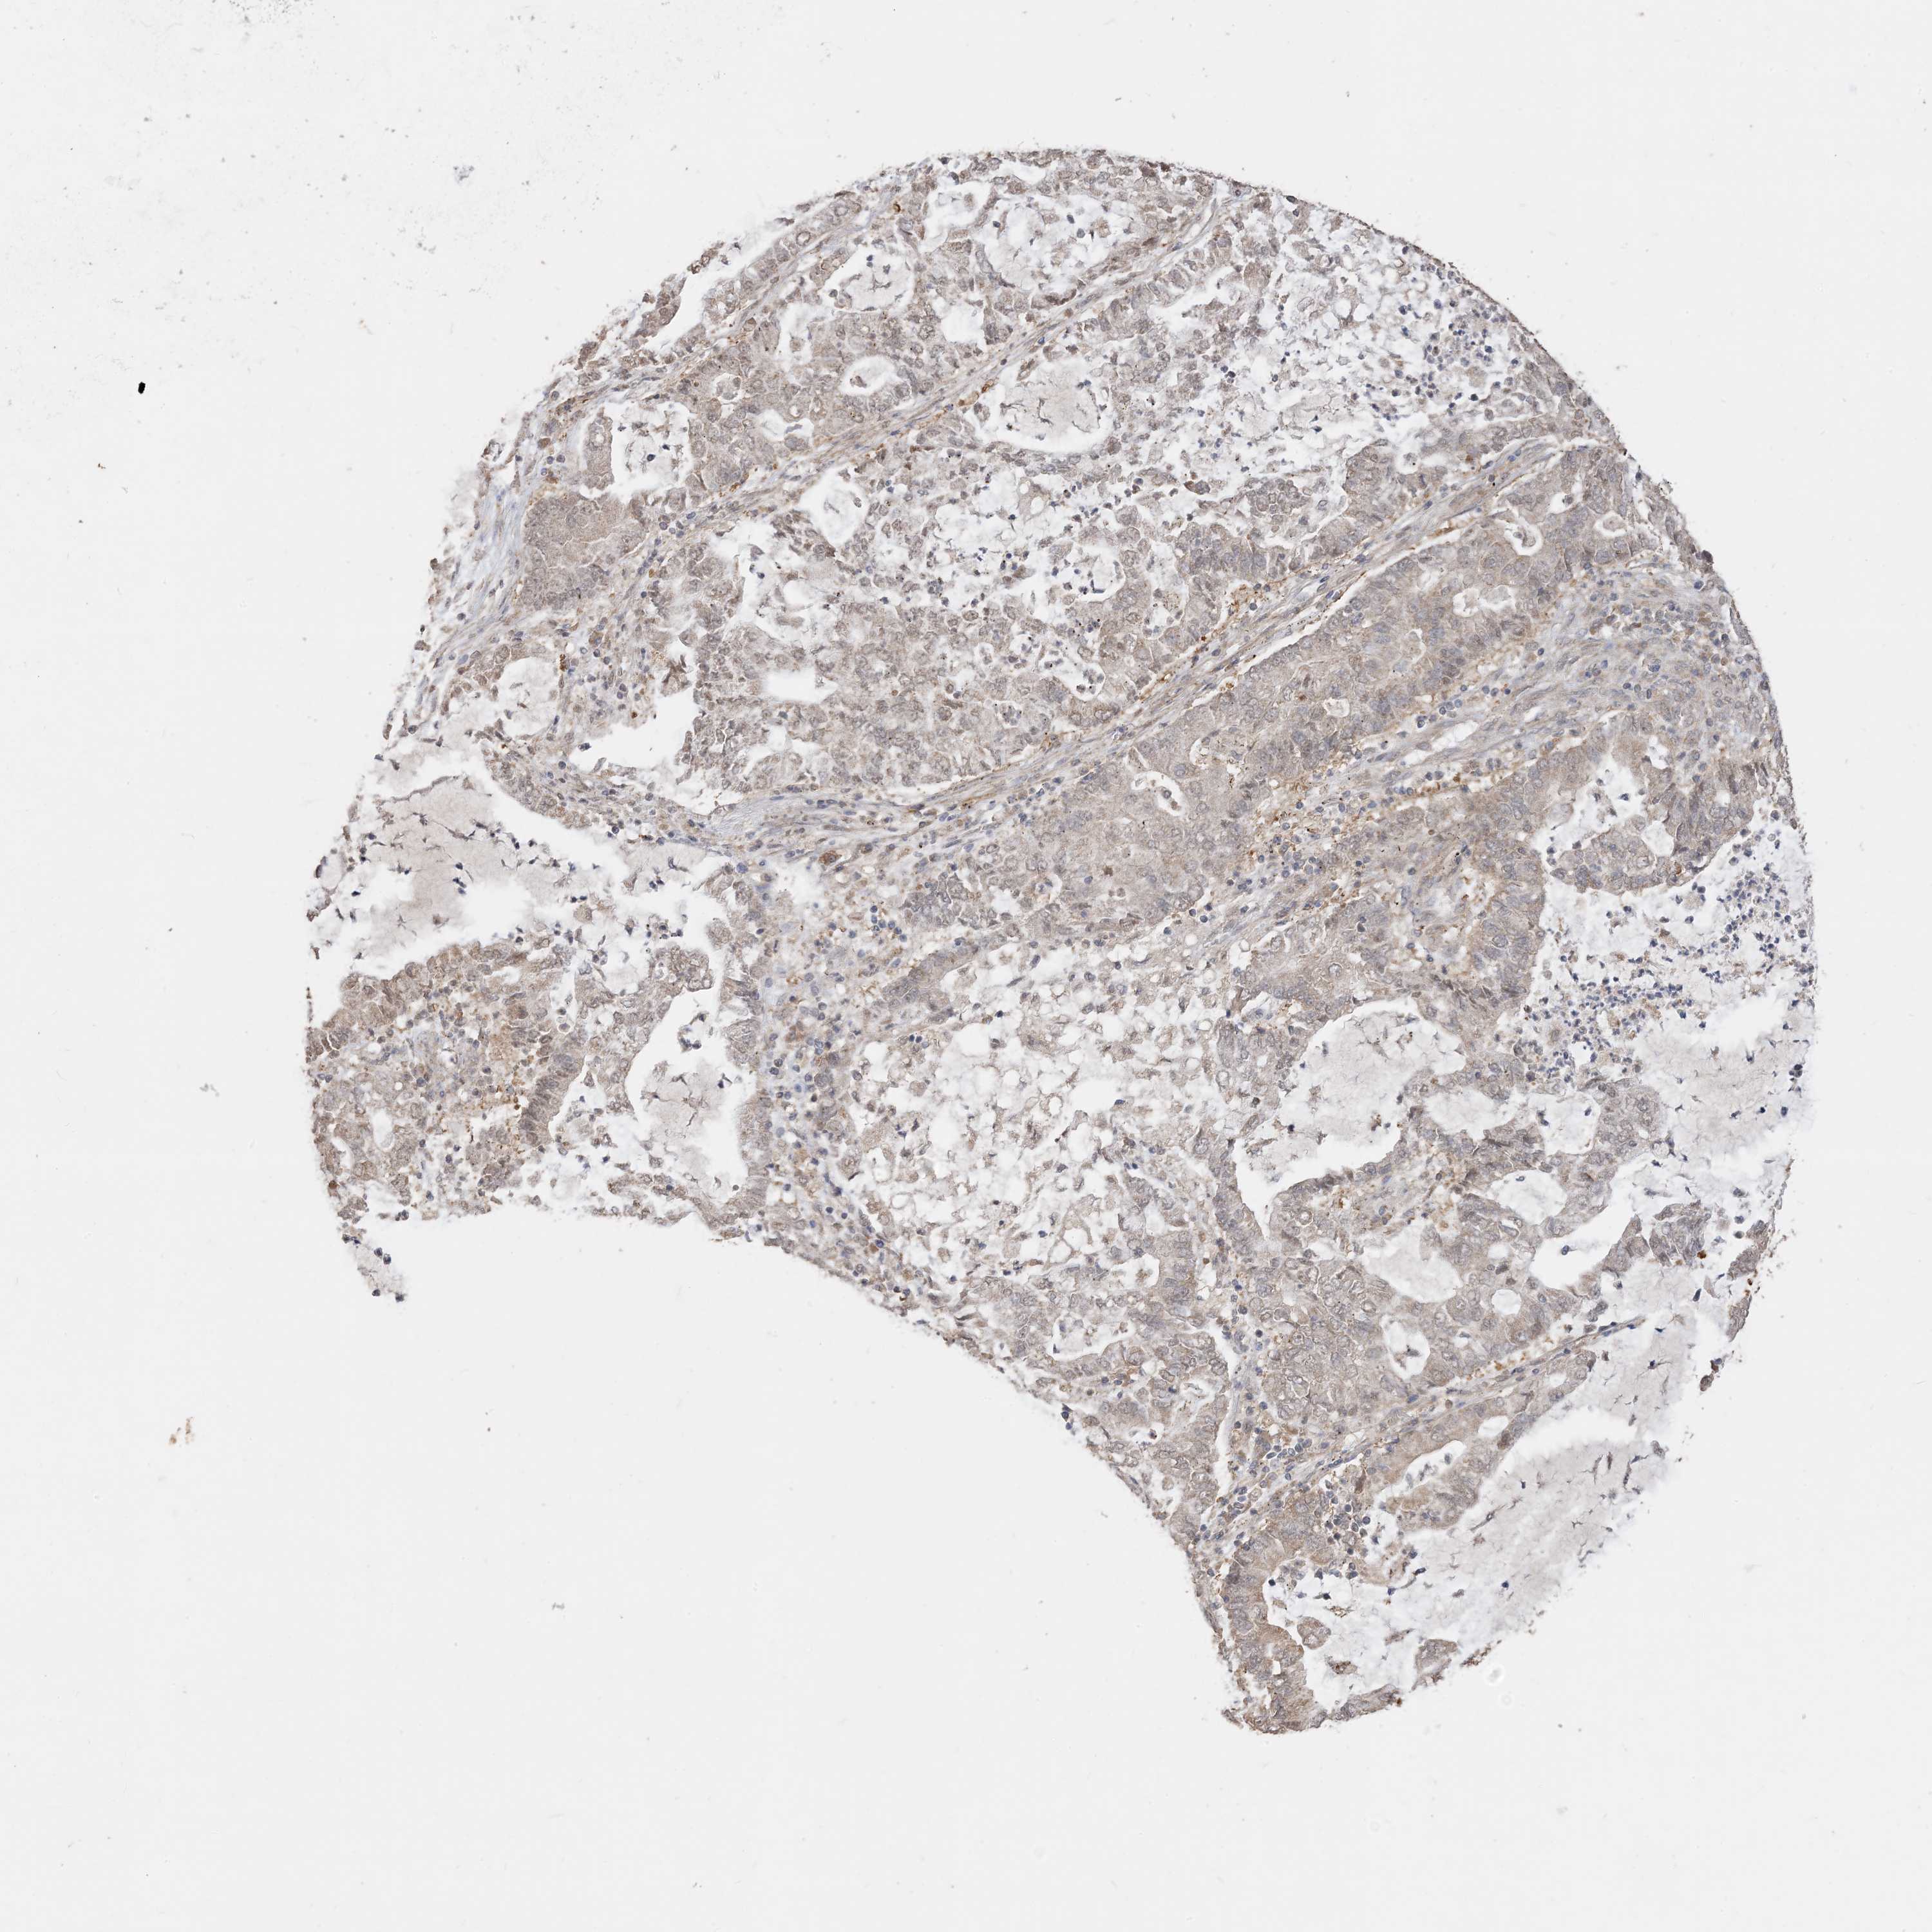

CANCER LUNG CANCER Show tissue menu

LUAD TCGA LUAD VALIDATION LUSC TCGA LUSC VALIDATION PROTEIN LUAD CPTAC PROTEIN LUSC CPTAC PROTEIN EXPRESSION

LUNG ADENOCARCINOMA (TCGA) - Interactive survival scatter ploti

The Survival Scatter plot shows the clinical status (i.e. dead or alive) for all individuals in the patient cohort, based on the same data that underlies the corresponding Kaplan-Meier plots. Patients that are alive at last time for follow-up are shown in blue and patients who have died during the study are shown in red.

The x-axis shows the expression levels (FPKM) of the investigated gene in the tumor tissue at the time of diagnosis. The y-axis shows the follow-up time after diagnosis (years). Both axes are complimented with kernel density curves demonstrating the data density over the axes. The top density plot shows the expression levels (FPKM) distribution among dead (red) and alive patients (blue). The right density plot shows the data density of the survived years of dead patients with high and low expression levels respectively, stratified using the cutoff indicated by the vertical dashed line through the Survival Scatter plot. This cutoff is automatically defined based on the FPKM cutoff that minimizes the p-score. The cutoff can be changed by dragging the vertical line or by entering a cutoff value in the square labeled "Current cut-off".

Under the Survival Scatter plot the p-score landscape (black curve; left axis) is shown together with dead median separation (red curve; right axis). Dead median separation is the difference in median mRNA expression between patients who have died with high and low expression, respectively. It is calculated as follows: median FPKM expression of dead patients with high expression - median FPKM expression of dead patients with low expression. This is intended to aid the user in visually exploring custom cutoffs and the associated p-scores and dead median separation.

Individual patient data is displayed and can be filtered by clicking on one or more of the category buttons on the top of the page. Categories describing expression level and patient information include: high, low, alive, dead, female, male and tumor stages. The scale of the x-axis can be toggled between linear and log-scale by clicking on the "x log" button. Mouse-over function shows TCGA ID, patient information and mRNA expression (FPKM) for each patient.

& Survival analysisi

Kaplan-Meier plots summarize results from analysis of correlation between mRNA expression level and patient survival. Patients were divided based on level of expression into one of the two groups "low" (under cut off) or "high" (over cut off). X-axis shows time for survival (years) and y-axis shows the probability of survival, where 1.0 corresponds to 100 percent.

SIRT3 is not prognostic in Lung Adenocarcinoma (TCGA)